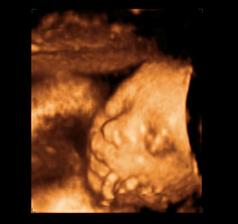

26 tt../1.4.2009/ naša paulínka je stráášne zlatá, boli sme si pozrieť na 4D utz. ..tvárila sa veľmi dôležito, až nafúkano...hehe..vôbec sa nechcela usmievať... nakoniec sa nám aj zasmiala...v brušku veľmi vyvádza, maminke dosť vytláča všetky časti telíčka, čo je niekedy aj dosť bolestivé...ale vydržíme, drobečkovi je tam určite tiež pritesno..a ešte aj stále viac a viac bude... strááášne sa na ňu tešíme🙂))